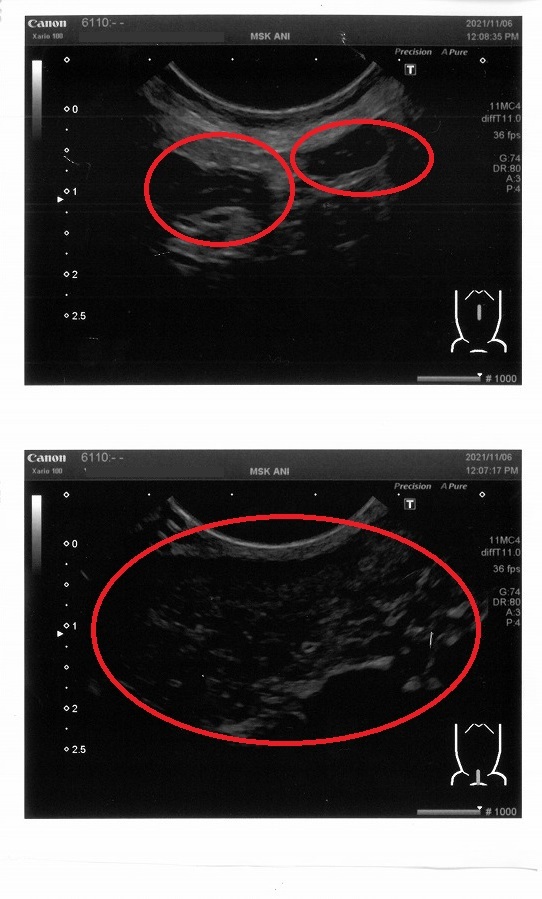

上の画像は腸が炎症を起こしている様子だそうです。

下の画像は赤丸の中がほどんど腫瘍で『肉腫』の可能性もあるとのことでした。